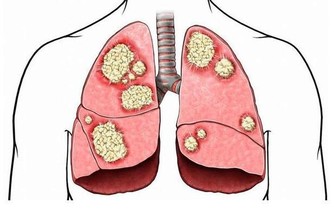

可以治療身體的酸痛、便秘、感冒、頭痛、

增強抵抗力、加速創傷恢復、防治心血管疾病、

治療風熱感冒、防治腎結石、袪痰、補鈣、

治療風濕病、懷孕止吐、婦科疾病、退燒。